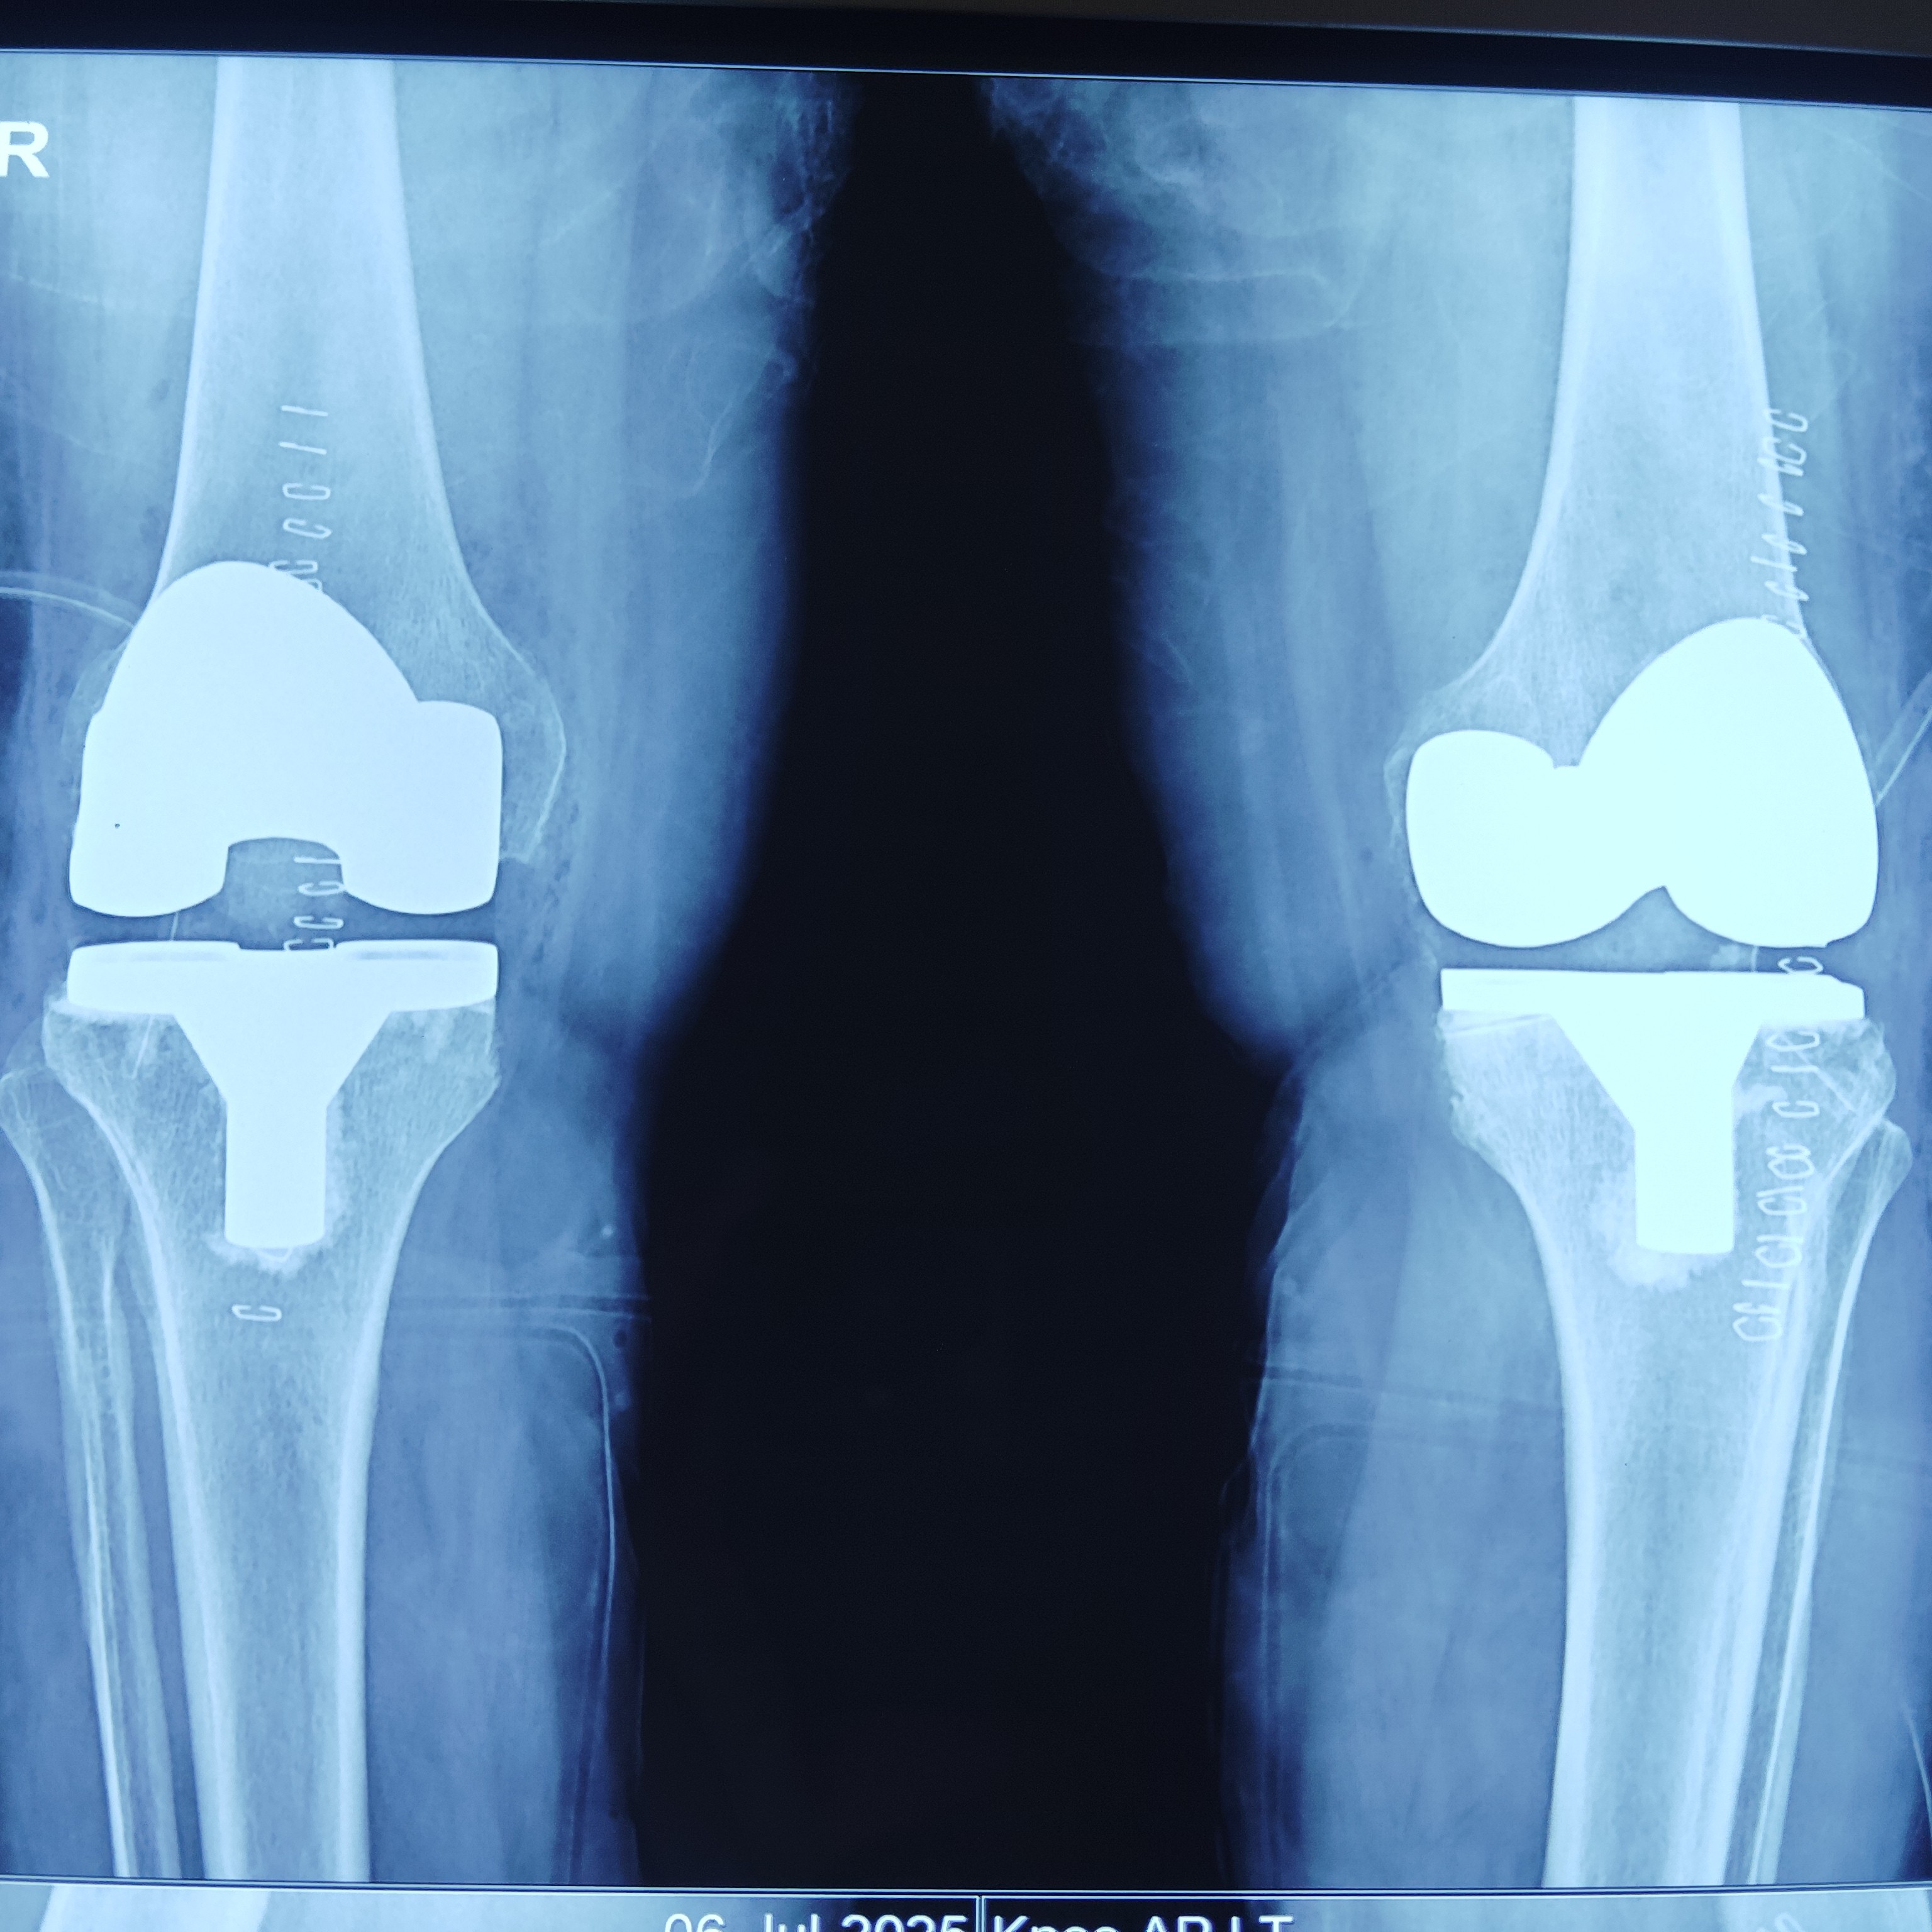

knee replacement in greater Noida